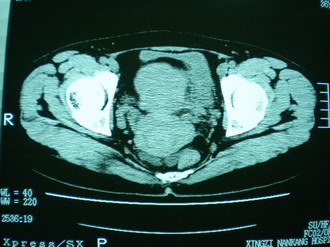

子宫明显前倾,增大,宫颈增大呈分叶状。子宫直肠窝见不规则形水样低密度。(膀胱胀尿不理想)

考虑:1、宫颈部占位;

2、子宫直肠窝少量积液(盆腔炎所致)。

考虑:1、宫颈部占位(宫颈癌?);

2、子宫直肠窝少量积液。

1、前曲子宫,2、宫颈部占位?3、盆腔及右输卵管积液?宫内积血?4、左侧卵巢囊肿。